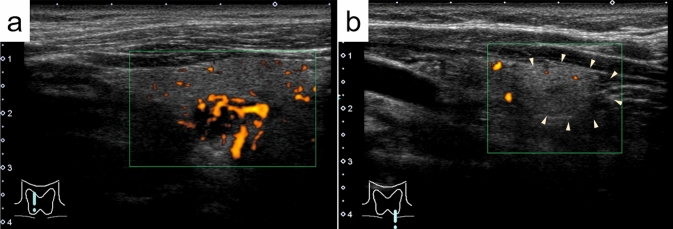

Results: Ultrasonography revealed a lipoadenoma detection rate of 20.0%. This increased to 80.0% at re-examinations performed after obtaining information from other imaging modalities. Compared with parathyroid adenoma cases with no adipocytes or few adipocytes, the frequencies of ill-defined margins, iso- and/or hyperechogenicity, heterogeneous consistency with a two-tone pattern, poor vascular flow, no polar artery, and no hyperechoic line were significantly higher in parathyroid lipoadenoma cases. The hyperechoic and isoechoic areas in tumors with a two-tone pattern correspond to adipocyte- and parathyroid cell-rich areas, respectively. The lipoadenoma tumor sizes measured using ultrasound tended to be smaller than the actual sizes.

Abstract Image